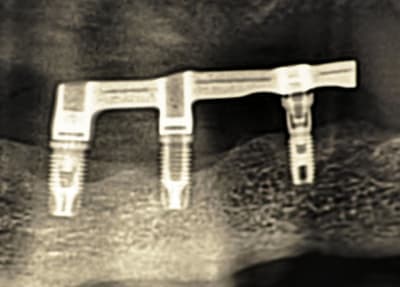

Patiente de 90 ans, dont les Implants ont été posés il y a plus de 20 ans et qui supportent une barre transvissée. Deux vis ont été perdues.

-Est ce des implants BRANEMARK ?

une petite rétro pour les 2 implants avec hex externe?

mais çà ressemble beaucoup à des Branemark (Nobel) mk3 (mais j'aimerais pouvoir te confirmer à 100%, là je suis sûr à 80%)

celui de droite (donc sur 33 si j'ai bien suivi) c'est un Screwvent Zimmer (certain 100%) avec son multiunit vissé dessus, donc ce que tu cherches c'est une vis pour multiunit...à commander chez zimmer-biomet

Ta barre est posée sur deux "systèmes" :

- en 41 43 en direct implant sur du Branemark (à confirmer comme le dit Pluton). Vis longue M2.

- en 33 sur un pilier type Multi Unit sur implant Zimmer Screwvent. Vis courte M1.4

Je viens de vérifier avec mon prothésiste en vissant des analogues au labo. Il y a bien deux systèmes implantaires : 2 Branemark et 1 Screwvent Zimmer avec un pilier Multi Unit ....